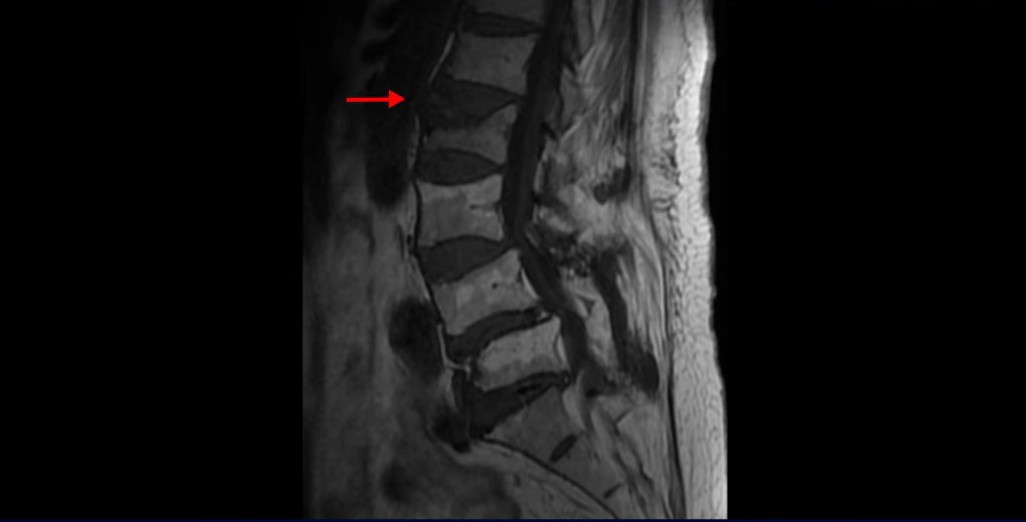

이 환자분은 협착증 수술 예약을 날짜까지 잡아놓고 넘어지면서 압박골절이 발생하고 협착증 증상 즉, 골반과 다리증상이 심하게 악화됩니다. 이분 MRI를 보시면 척추 2번 뼈에는 넘어지면서 생긴 척추압박골절이 보입니다.

3번과 4번 마디에는 황색인대 골화증으로 인한 중심성 협착이 보입니다.

4번과 5번 마디는 전방전위증이 있고 15년 전 허리수술을 받은 적이 있어서 척추 후관절과 후궁을 제거한 흔적들이 보입니다.

또 5번 1번에는 왼쪽 신경가지가 빠져나가는 추간공 즉 신경구멍이 많이 좁아져 있습니다. 이 환자분은 허리통증과 함께 왼쪽 다리 증상이 심하셨는데 이것 때문인 것으로 보입니다.